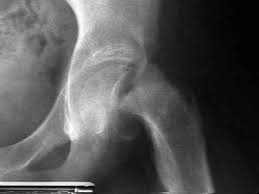

Felnőttkori combfej elhalás

A felnőttkori combfej elhalás lehet baleset, combnyaktörés következménye, vagy lehet ismeretlen eredetű. Az első esetben a kezelés egyértelműen műtét, a második esetben a betegség lefolyása lassú, kezelés nélkül fokozatosan romlik a beteg állapota a csípőfájdalomtól, a súlyos sántításig.

A fiatal, felnőttkori combfejnecrosis 80%-ban a férfiakat érinti. Tünetei kezdetben nem jellemzőek, a korai stádiumban tünetmentes is lehet, vagy csak átmeneti csípőizületi fájdalmak jelentkezhetnek, átmeneti jelleggel. A bizonytalan, kellemetlen csípő-fájdalom gyakran éjszakai jelentkezik, s nehéz a végtagnak nyugalmi pozíciót találni. Máskor erőteljes, de nem állandó jellegű a csípőízületi fájdalom, amely folyamatosan és gyorsan progrediál, majd később állandósul. A végeredmény az állandósult sántítás, az egyre fokozódó csípőizületi mozgáskorlátozottság következtében.

Fontos hangsúlyozni, hogy a megbetegedés gyakran (40–80%-ban) kétoldali, de a megjelenés nem mindig egy időben történik.

A fiatalkori combfejelhalás oka az esetek egy részében tisztázatlan, máskor trauma, gyógyszer adagolás, alkohlizmus vagy egyéb betegség áll a háttérben.

kiváltó októl függetlenül a combfej vérellátása zavart szenved, a fejben csontelhalás jön létre, későbbi szakaszban a fej terhelési felszíne beroppan, a fájdalom jelentősen fokozódik, az izület mozgása súlyosan besűkül.

Diagnosztikájában a kétirányú rtg, CT, MR és csontscintigráfia segít.

A terápia annál hatékonyabb, minél korábbi stádiumban történt a betegség felismerés és kezelésbe vétele.

Kezelésében konzervatív módszerként tehermentesítés, gyógyszeres kezelés jön szóba, amely egyrészt a combfej vérkeringését javítja, illetve olyan gyógyszerek adagolása, amelyek a csont-anyagcserét javítják.

Ennek eredménytelensége esetén műtéti kezelés, combfej felfúrés, érnyeles lebeny plasztika végső stádiumban izületi protézis beültetés.